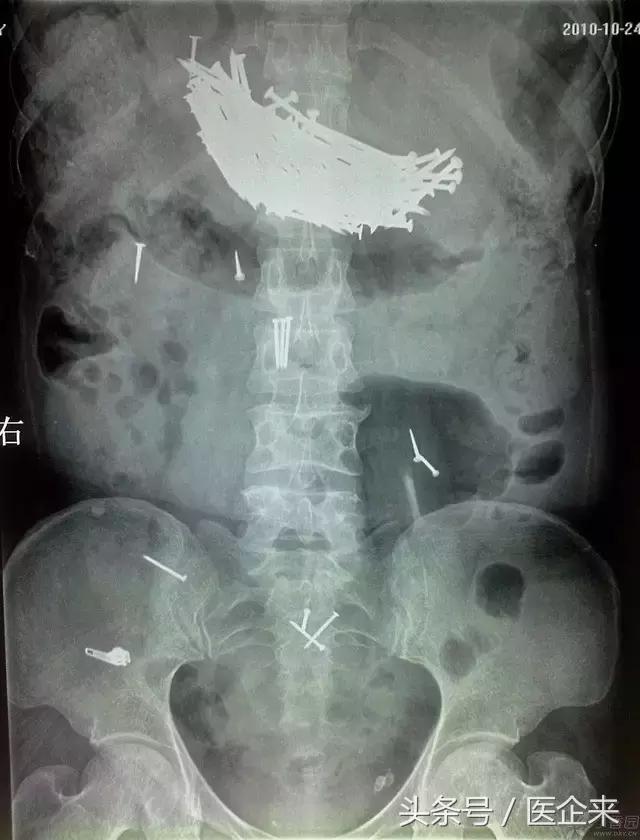

10. 经口吞入大量钉子(一句话,正常人干不出这事...)